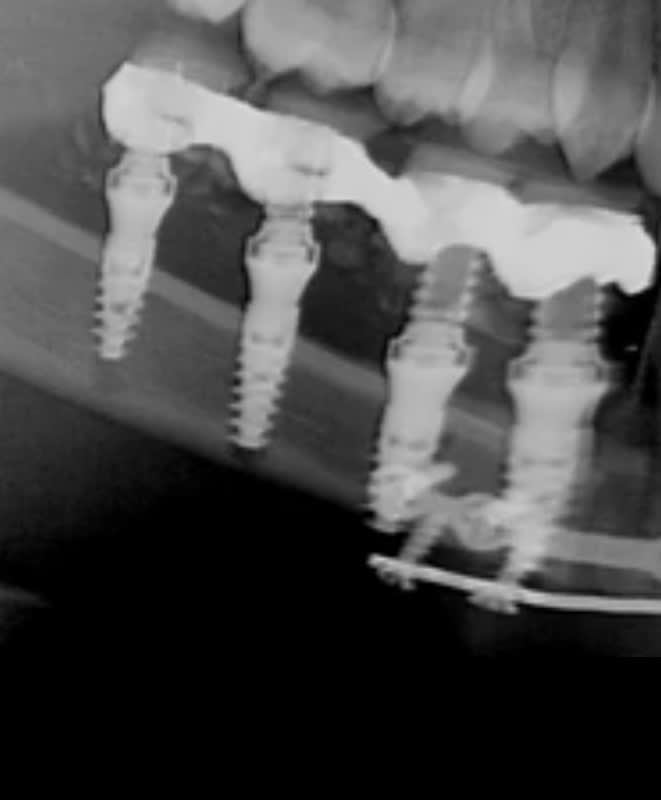

l implant le plus distal avec ces 5 spires en dehors de l os... chapeau l artiste.

une gestion de la profondeur de forage aux petits oignons...

je sais pas de quoi tu te ventes en montrant ce travail... très sincèrement.

apres je vais pas épiloguer, le chirurgien a probablement fait ce qu il a pu avec ce qu on lui a mis a disposition . mais montrer ca comme la panacée alors que les deux implants distaux sont particulièrement mal enfouis, c est vraiment a ce tordre de rire.

Connais tu les caractéristiques de l'os dans le quel ces implants sont posé ?

je comprend que ce cas sort de ton champ de compétence et que tu n'es pas en mesure de lire correctement la panoramique et comprendre cette intervention. Aussi je viens de faire un montage avec des éléments post opératoire pour te montre qu'aucun implant est positionné hors du péroné.

Pour le reste, prolongement du forage position bi-corticale des implants cela ne me semble pas opportun de te l'expliquer.

les deux implants distaux sont super mal enfouis posit... c est mauvais. tres mauvais meme.

j oserais meme pas presenter un cas aussi mal réalisé ;)

j espère sincèrement que vous avez repris le travail par la suite.